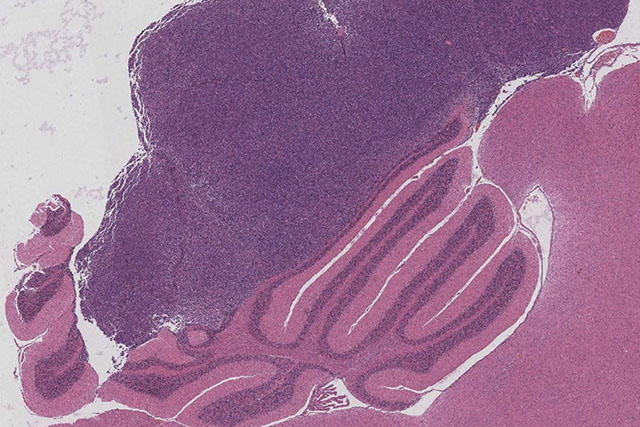

Microscope image of medulloblastoma